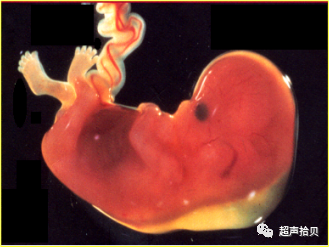

2)21- 三体综合征动物模型

16三体小鼠人类21三体的动物模型——16三体小鼠,有心脏畸形和淋巴管异常。

在 14-16天,出现颈后皮下液体聚集。